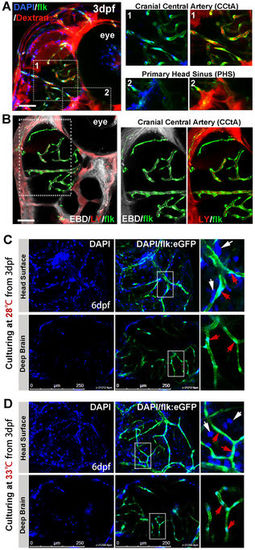

Imaging of functional BBB in 3dpf and 6dpf zebrafish. (A,B) The Dextran Texas Red (70,000?MW, 1?mg/ml), Evans Blue Dye (EBD, 961?MW, 5?mg/ml), Lucifer Yellow (LY, 457?MW, 4?mg/ml) and DAPI (350?MW, 1.5?mg/ml) were mixed and injected into the circulation of 3dpf flk:eGFP or flk:mCherry embryos (5?nl/fish, green indicating endothelial cells) from caudal vein (CV). Z-stack confocal living images of the cerebral capillaries and segmental capillaries (Fig. S2A) were obtained at 30?60?min after injection. (A, area1) Dextran and DAPI were restrained in cerebral capillaries (CCTA), but were leaked out from primary head Sinus (A, area2) and segmental capillaries (Fig. S2A). (B) CBD (white) and LY (red, pseudocolor) were restrained in CCTA (mCherry was pseudocolored as green). Areas in dotted boxes were magnified right. (C) DAPI was injected into the circulation of 6dpf embryos (maintained at 28?�C) from CV. Z-stack confocal living images were taken at 1?h post injection. White arrows indicating nucleus of host cells neighboring to vessels; Red arrows indicating endothelial nucleus. (D)DAPI was injected into the circulation of 6dpf embryos (normally maintained 3dpf zebrafish were shifted to 33?�C for 3days) from CV. Z-stack confocal living images were taken at 1?h post injection. White arrows indicating nucleus of host cells neighboring to vessels; Red arrows indicating endothelial nucleus. EXPRESSION / LABELING: